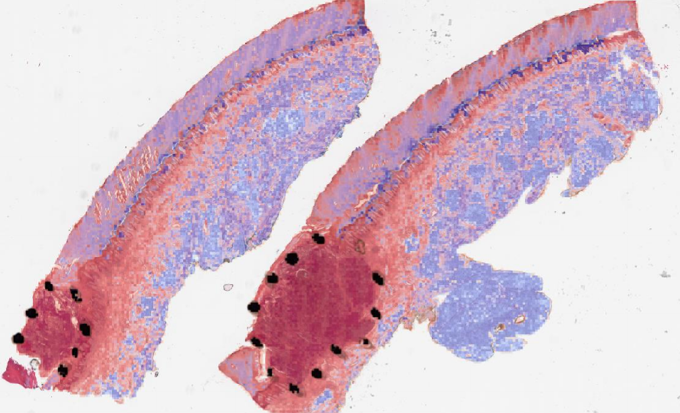

Explanations for the figures. Figure 2 shows one representative sample of annotations (black dot regions) as well as without annotations. Visualization maps of two samples from the melanocytic skin tumor dataset are shown in figure 3 and figure 4. Figure 3 shows the three types of figures of the largest ROI region from melanoma found by the proposed method. Figure 4 is the same for the nevus sample. The overlap map highlights top-ranked patches in a WSI and masks other area with a transparent blue color. The percentage of highlighted patches equals (the annotated ratio). The boundary map shows the boundary of the largest ROI cluster based on the highlighted patches, where the highlighted patches are clustered by OPTICS algorithm from Ankerst et al. (1999). The last one is a heatmap where red covers regions that have high predicted scores and blue covers regions that have low predicted scores.

(a) Boundary of the largest predicted ROI region

(b) Overlay

(c) Heatmap